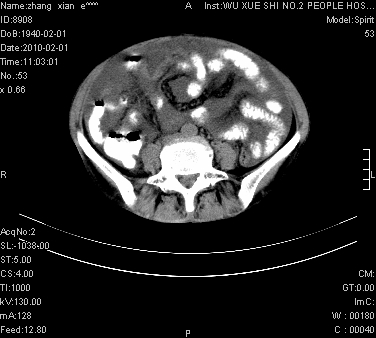

标题: CT24434:70岁 女 腹胀,腹水原因待查 [打印本页]

标题: CT24434:70岁 女 腹胀,腹水原因待查

大量腹水,脾脏囊性占位,子宫颈占位,右侧腹股沟淋巴结肿大,建议+c,先查妇科。

腹盆腔大量积液,子宫增大,子宫颈增大外形不规则,内见低密度影,膀胱后壁显示不清,右腹股沟肿大淋巴结,脾脏囊性占位,子宫颈占位,子宫颈癌?建议增强。

腹盆腔大量积液,子宫增大,子宫颈增大外形不规则,内见低密度影,膀胱后壁显示不清,右腹股沟肿大淋巴结,脾脏囊性占位,子宫颈占位,子宫颈癌?建议增强。支持!